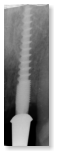

Versorgung einer Molarenlücke mit zwei Champions 3,0 mm

Durchmesser, Längen 12 mm und 16 mm und einer sofort angefertigten

Cerec-Krone in zwei Stunden. Die Krone ist rotationsgesichert,

ästhetisch wie ein natürlicher Zahn zu versorgen und auch im

Hauptbelastungszentrum sofort belastbar.